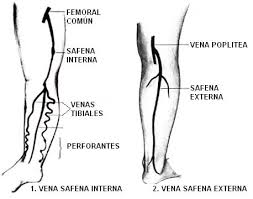

329 × 361 - gimolimpo.com

{"cb":3,"cl":9,"cr":9,"ct":3,"id":"xpk45dB8E7I8sM:","isu":"gimolimpo.com","itg":0,"ity":"jpg","oh":361,"ou":"http://www.gimolimpo.com/Paginas/feblectomia_archivos/image007.jpg","ow":329,"pt":"FEBLECTOMIA","rid":"ZemkA-aU5uHAnM","rmt":0,"rt":0,"ru":"http://www.gimolimpo.com/Paginas/feblectomia.htm","s":"óptima

relación

costo/beneficio","sc":1,"st":"Olimpo","th":235,"tu":"https://encrypted-tbn0.gstatic.com/images?q\u003dtbn:ANd9GcTGBYVUqIaQnxn14lGu1tBPjfbHVvdDHcHstHMXtyqikZScWr_ocw","tw":214}

379 × 281 - gimolimpo.com

{"id":"yi_QeHfQlQD5hM:","isu":"gimolimpo.com","itg":0,"ity":"jpg","oh":281,"ou":"http://www.gimolimpo.com/Paginas/feblectomia_archivos/image003.jpg","ow":379,"pt":"FEBLECTOMIA","rid":"ZemkA-aU5uHAnM","rmt":0,"rt":0,"ru":"http://www.gimolimpo.com/Paginas/feblectomia.htm","s":"Tipos

de

tratamiento","sc":1,"st":"Olimpo","th":193,"tu":"https://encrypted-tbn0.gstatic.com/images?q\u003dtbn:ANd9GcTl_DJI550zaYSZMH-miDVhWY4UK03LOi9ze-1B_FsuneyxG_grOQ","tw":261}

231 × 397 - gimolimpo.com

{"cl":3,"id":"Ofxp5Rburirp3M:","isu":"gimolimpo.com","itg":0,"ity":"jpg","oh":397,"ou":"http://www.gimolimpo.com/Paginas/feblectomia_archivos/image005.jpg","ow":231,"pt":"FEBLECTOMIA","rid":"ZemkA-aU5uHAnM","rmt":0,"rt":0,"ru":"http://www.gimolimpo.com/Paginas/feblectomia.htm","s":"Flebectomía

ambulatoria, es la safenectomía, modificada por el Dr. Oesch, suizo,

que consiste en efectuar la exéresis de la vena, sin lesionar los

tejidos

...","sc":1,"st":"Olimpo","th":294,"tu":"https://encrypted-tbn0.gstatic.com/images?q\u003dtbn:ANd9GcQTaZ5oRKfEvwuBOC5RWCE4GIQU2e4MrfYhpJMx2vBMlbt5qVXNew","tw":171}